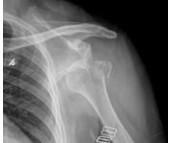

肩關節脫位最常見,約占全身關節脫位的50%,這與肩關節的解剖和生理特點有關,如肱骨頭大,關節盂淺而小,關節囊松弛,其前下方組織薄弱,關節活動范圍大,遭受外力的機會多等。肩關節脫位多發生在青壯年、男性較多。

- 常見癥狀:肩關節活動受限、肩關節痛、肩節后脫位、肩部運動受限、搭肩試驗陽性